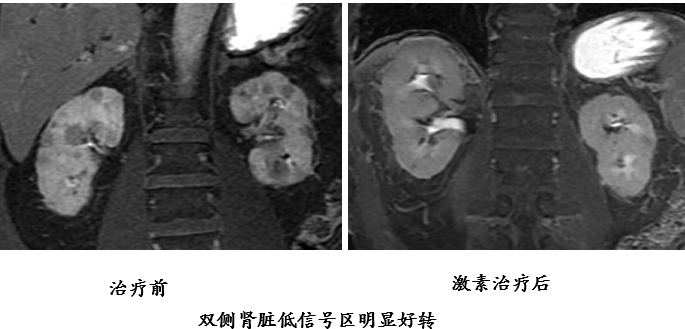

垂体受累

75 岁女性。A 图:双侧泪腺增大,轴位 T2 像显示低信号。B 图冠状位显示左侧眶下神经受累增粗;矢状位 T1 垂体柄增粗, 后叶高信号消失